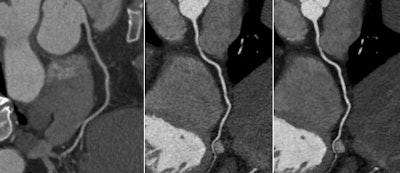

The study compared CCTA images between 185 patients whose kV settings were based on a BMI protocol and a group of 197 patients whose kV settings were based on the APSCM automatic protocol. The researchers processed the data from the latter group using two reconstruction techniques: filtered back projection and SAFIRE.

According to the results, images from the APSCM group with SAFIRE showed a significant reduction in image noise and a significant increase in Hounsfield units (HUs), contrast enhancement, signal-to-noise ratio, and contrast-to-noise ratio compared with the APSCM group reconstructed with FBP (p < 0.0001) and with the BMI-based group (p < 0.001; except p = 0.002 for image noise).

Image noise was reduced by 29% on images obtained using APSCM with SAFIRE, and contrast-to-noise and signal-to-noise ratios increased by about 41%, compared with images from the APSCM group reconstructed using FBP, Suh and colleagues reported.

In the APSCM group with FBP, contrast enhancement of coronary arteries was 10% higher as measured by Hounsfield units than in the BMI-based group, though signal-to-noise and contrast-to-noise ratios were lower. The APSCM group with SAFIRE maintained a higher mean CT number by 9.8% and higher contrast enhancement by 9%, while also showing 21% higher ratios compared to the BMI-based group.

When FBP reconstruction was applied, the use of APSCM resulted in a 10% increase in mean vascular CT attenuation and contrast enhancement compared with the BMI-based group; however, image noise rose by 29% -- a result the authors attributed to the larger number of CT scans being obtained with 80 kV and 100 kV in the APSCM group.

The use of iterative reconstruction in the automated tube current modulation scans didn't change the vascular CT values or contrast enhancement, but reduced image noise by 29%, offsetting and even overcoming the effects of image noise in the lower-dose scans.